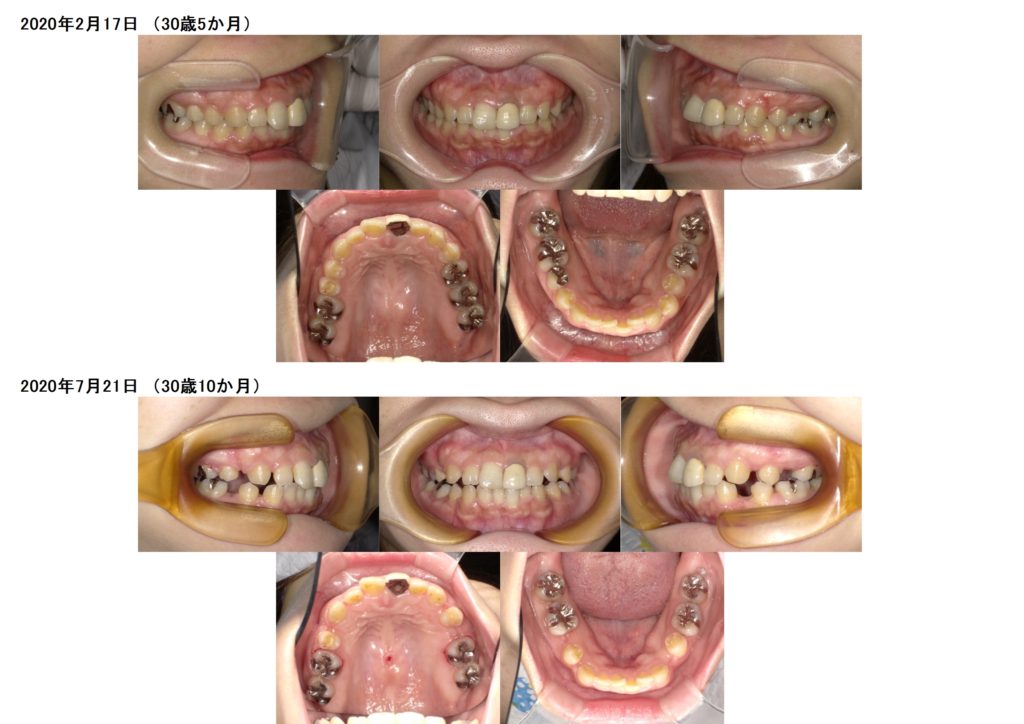

上の歯に乳歯が残っているので、その乳歯の抜歯と、その他永久歯を3本抜歯しての治療になります。

土台を維持しつつ、抜歯したスペースを4か月間動かしました。

随分と歯が動いたのが分かりますよね☆